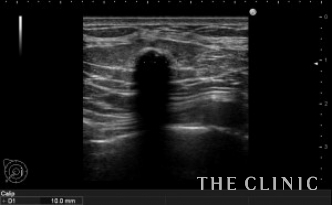

しこりの位置と、エコー所見です。

右は10mm